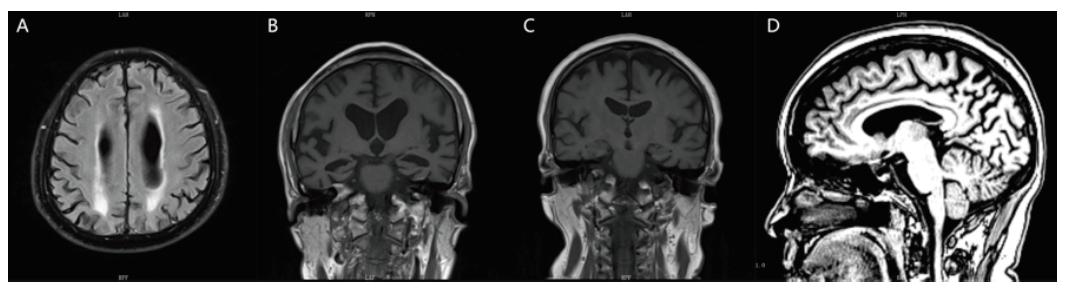

有12例患者的头颅结构影像表现为不同程度的额颞顶叶皮层萎缩,多为不对称性的,其中有8例患者出现不同程度的脑白质损害(图A)。所有患者均完成头颅MRI显影的内侧颞叶萎缩(MTA)视觉评分[5],有10例患者出现海马萎缩(图B);有4位患者的海马是正常的(图C),但均出现后扣带沟、顶枕沟增宽,后方扣带回和楔前叶萎缩的顶叶萎缩(图D);有1例患者未见明显的脑萎缩。

图A 病例8患者头颅MRI T2 FLAIR像脑白质损害融合成大的病灶;图B 病例8患者头颅MRI T1像冠状位见海马重度萎缩,MTA评分4级;图C 病例4患者头颅MRI T1像冠状位见海马正常,MTA评分0级;图D 病例4患者头颅MRI T1像失状位见后扣带沟、顶枕沟增宽,扣带回后方和楔前叶萎缩。

Fig.A T2-weighted Flair MRI images showing white matter lesions fused into large lesions in Case 8;Fig. B T1-weighted MRI images showing severe hippocampus atrophy in coronal position, and MTA score is 4 in Case 8;Fig.C T1-weighted MRI images showing normal hippocampus in coronal position, and MTA score is 0 in Case 4;Fig.D T1-weighted MRI images showing the posterior cingulate groove, parieto-occipital groove widening, cingulate back posterior and anterior cuneiform atrophy in sagittal position in Case 4.

不同的患者磁共振的表现差异较大,缺乏特异性;患者评估时的年龄越小,神经心理量表得分越高的,其磁共振的表现肉眼看有可能是正常的或者是只有轻度的顶叶萎缩。晚发型AD在结构核磁的表现主要是内侧颞叶萎缩,临床上常用的是目测法,即内侧颞叶萎缩(MTA)视觉评分:通过MRI冠状位,对萎缩的海马进行分级,从正常到严重萎缩分为0~4级[5]。MTA对鉴别晚发型AD的敏感性和特异性较高[17],但对于鉴别早发型AD缺乏特异性;早发型AD相对于晚发型AD,内侧颞叶萎缩不明显,而顶叶、外侧颞叶的改变更加突出[18]。可以对一个高度怀疑阿尔茨海默病的患者进行随访复查,观察内侧颞叶萎缩是否有进展;对于年轻的患者,需要注意有没有以后扣带沟、顶枕沟增宽为表现的顶叶萎缩。